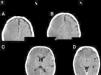

A las 24 h, el paciente persistió con los mismos síntomas neurológicos, por lo que se decidió realizar otra TC encefálica, la cual evidenció una lesión hipodensa difusa, con pérdida de la diferenciación corticosubcortical supratentorial derecha. Producía leve efecto de masa, con pérdida de los surcos de la convexidad y pequeños focos de hemorragia subaracnoidea. Estos hallazgos fueron interpretados como compatibles con isquemia aguda en evolución (fig. 1). La ecografía Doppler de vasos del cuello no mostró alteraciones.